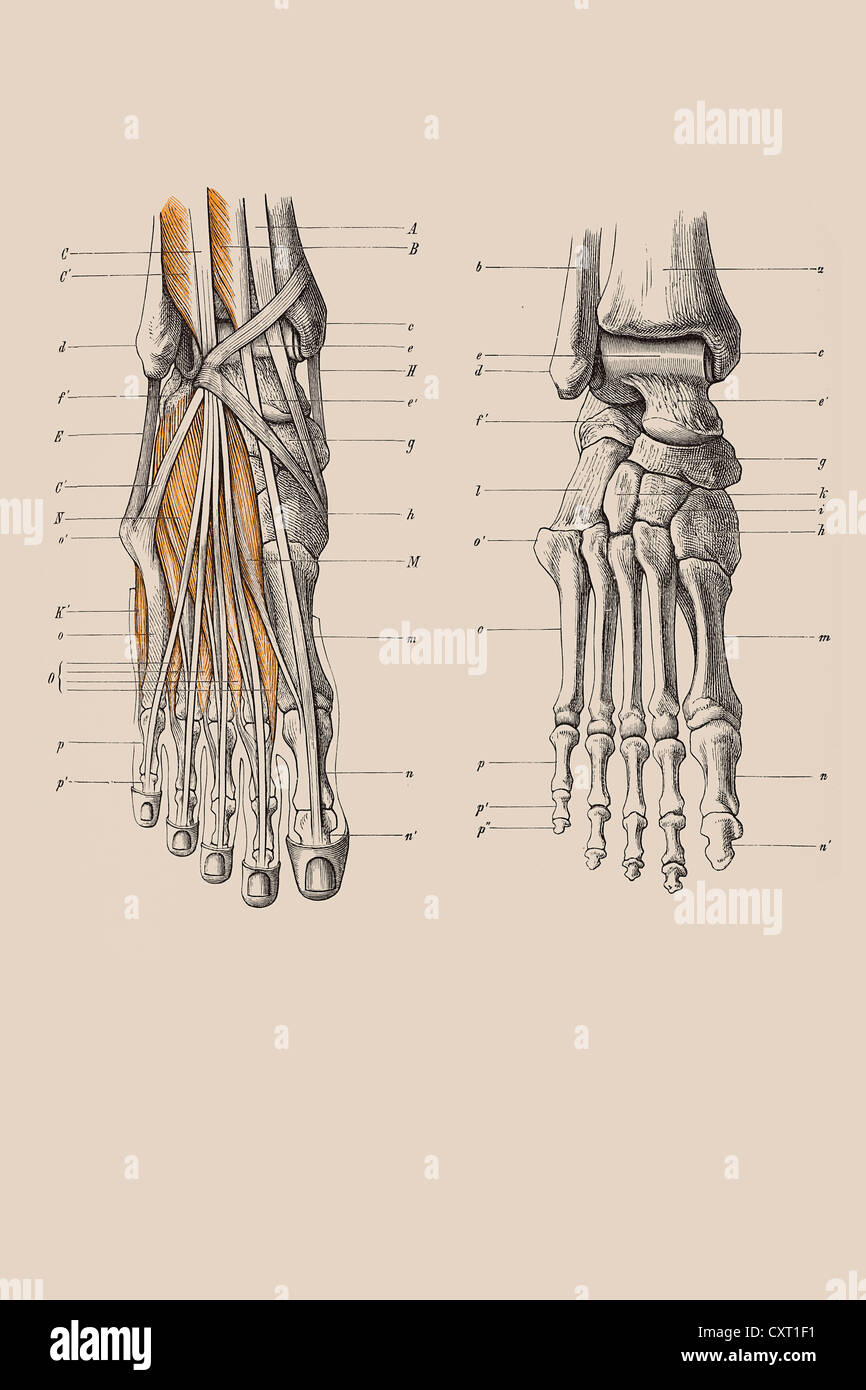

RFPR8GRD–19ème siècle illustration de la jambe gauche de l'avant après avoir enlevé la peau et le fascia. Publié dans Bilder-Atlas Conversations-Le Systematischer zum

RF2WNN754–Illustration médicale des principales parties des os du pied en vue antérieure, avec annotations.